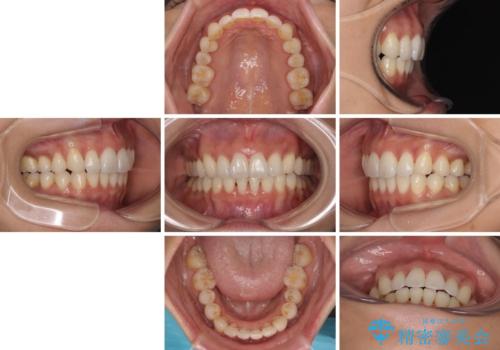

出っ歯になることなく、上下前歯が綺麗に接触する状態で仕上げることができました。